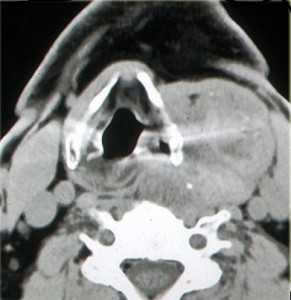

МРТ мягких тканей шеи. Т2-зависимая МРТ в аксиальной плоскости. Невринома.

Невриномы также располагаются между крупными сосудами, отодвигая их. Опухоль округлая, с четким контуром, хорошо контрастируется и в отличие от параганглиомы не содержит сосудистых включений.